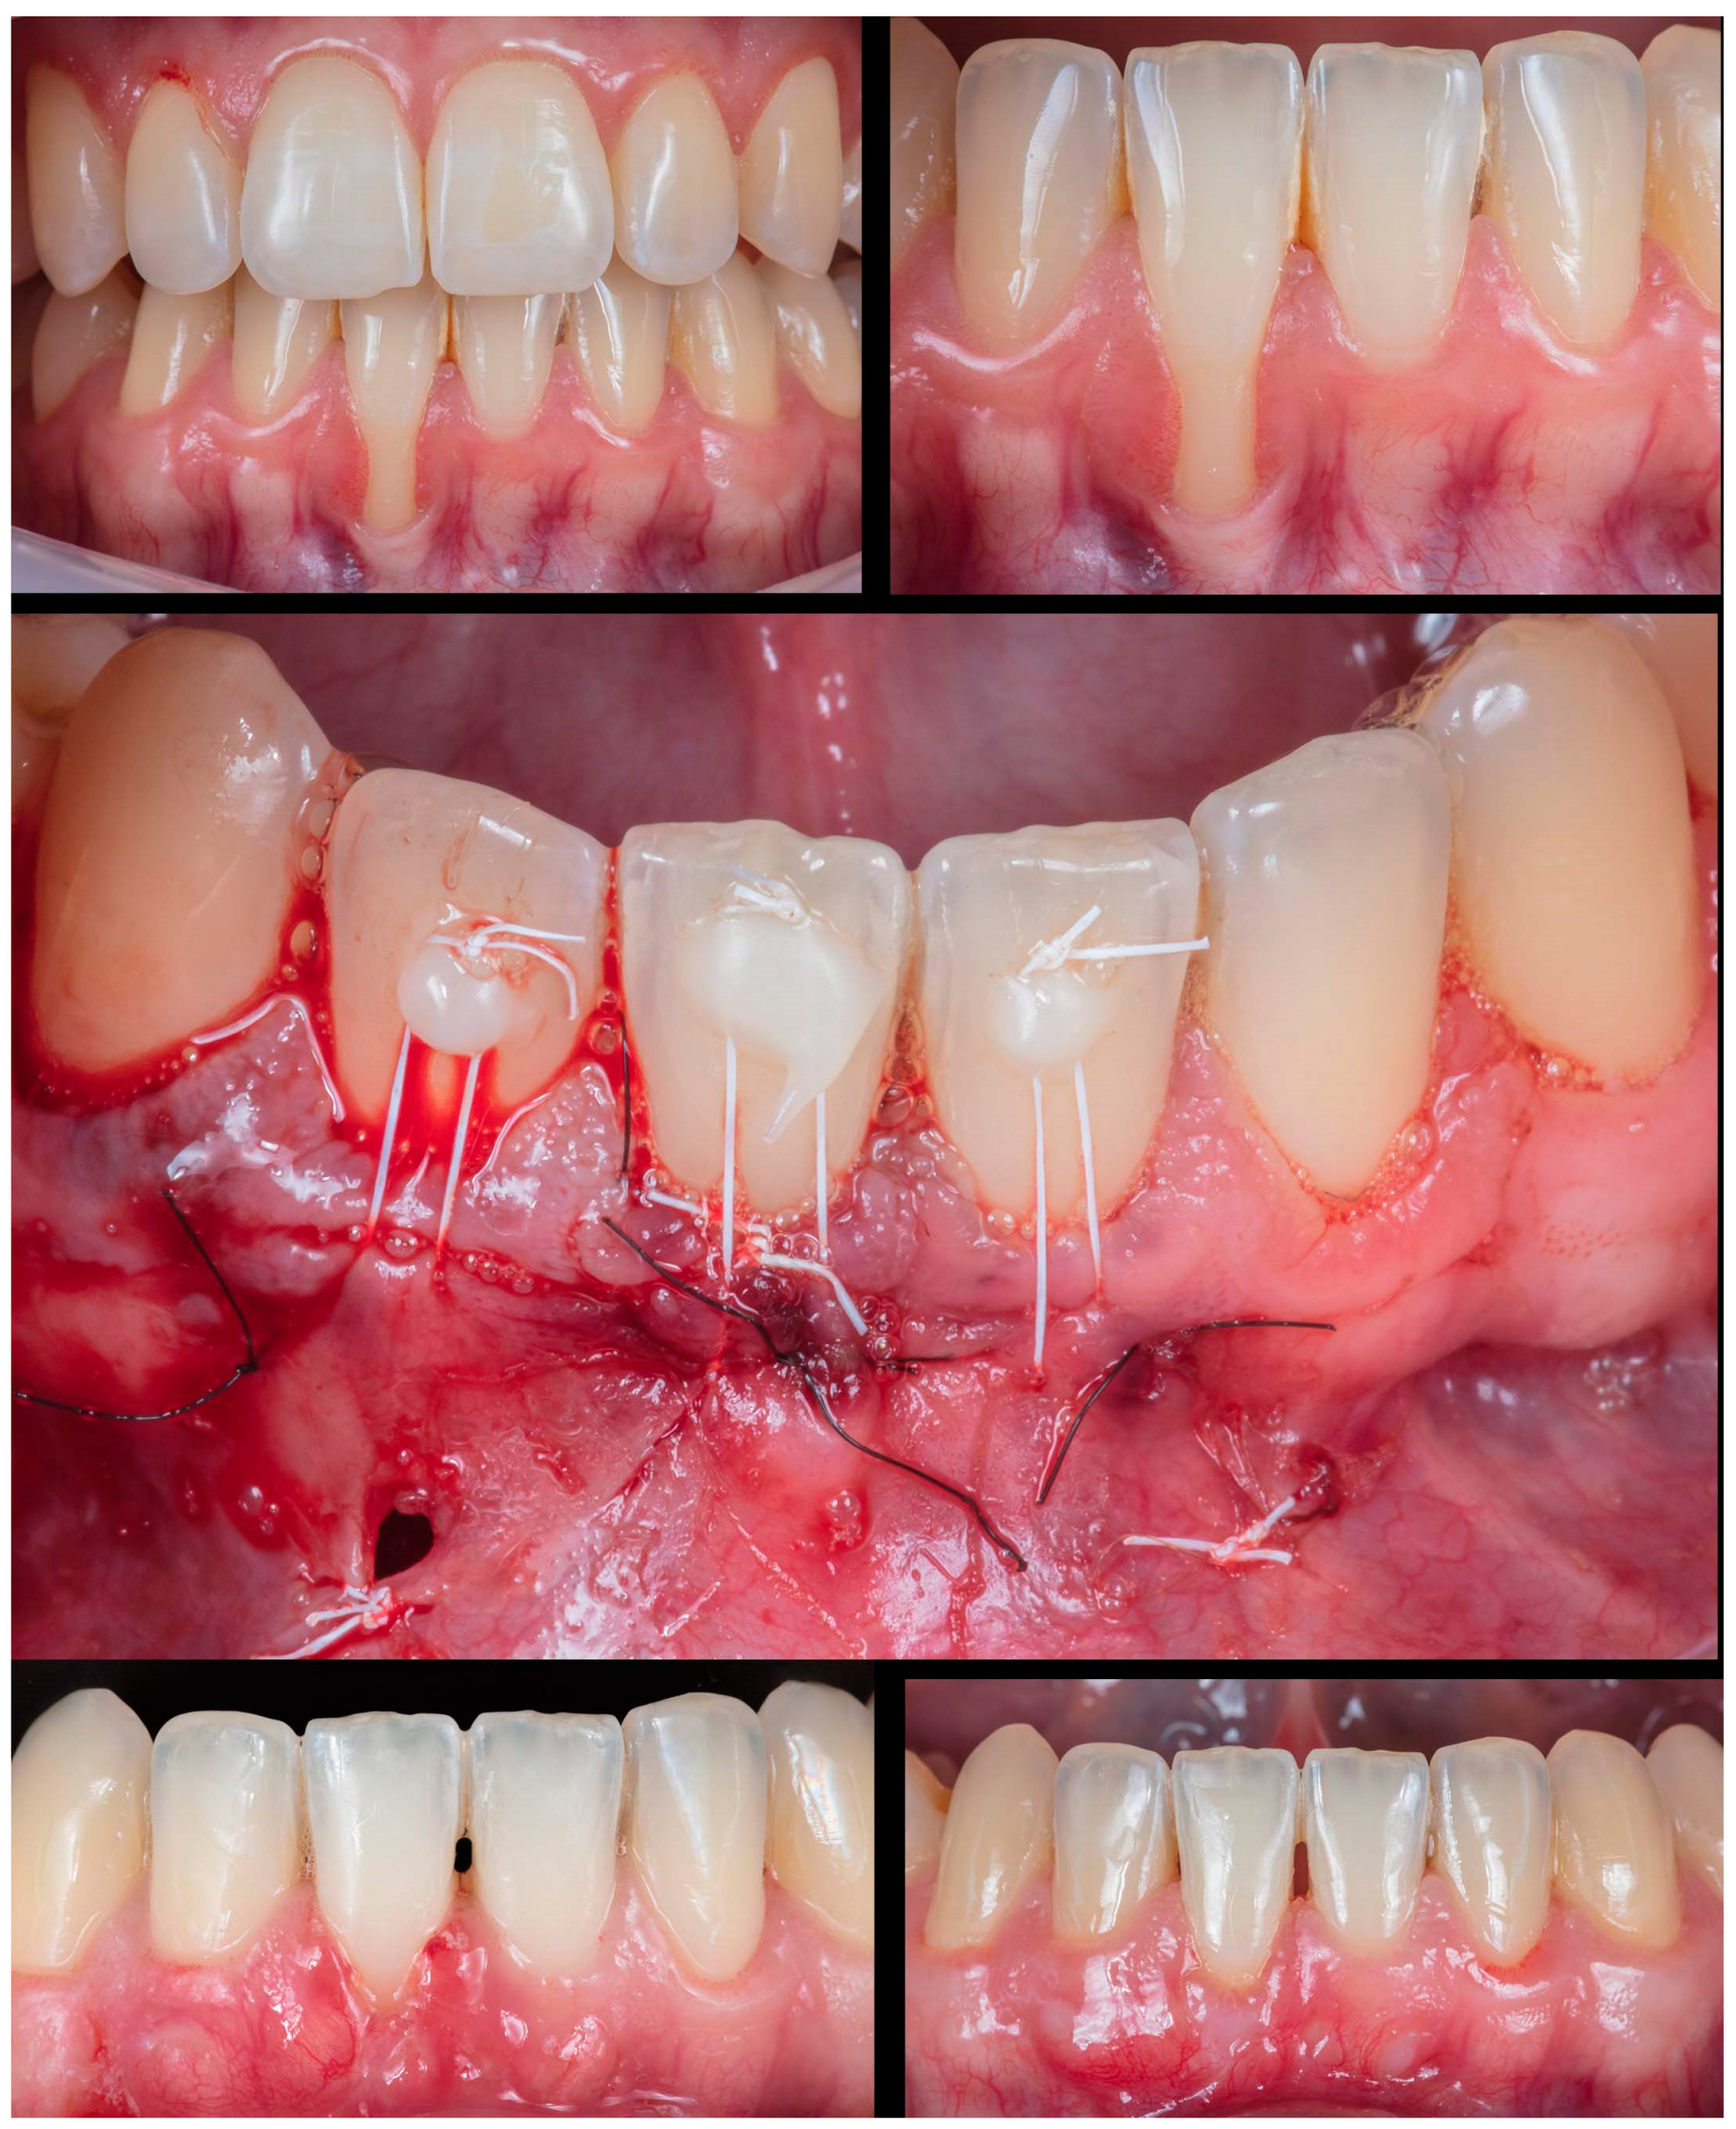

Figure 8.

Case 7 shows initial pictures of the GR defects (#12-#22); a picture showing the final aspect immediately after surgery; and the healing period after 14 days and 1 year.

Figure 8) differed from the rest because it involved an esthetic area in an anterior maxillary region. Even with a gingival RT1 in teeth #12-#22, respectively, with 1mm, 1.5mm, 2mm, and 1.5mm, teeth #11 and #21 presented a wide GR (3mm and 4mm, respectively). The case was conducted without adverse events using two linear vertical incisions on the distal to the central incisors. A buccal suture in the facial region of the teeth was made using composite. An adequate healing process was found after 7 days and 1 year, which was permitted by the tissue stability achieved in soft tissue management. The success rate was 100% for RC.